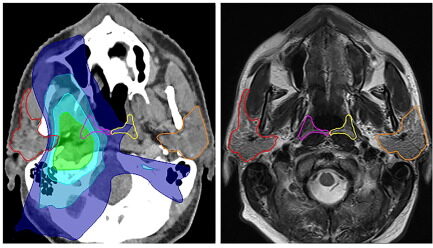

Фото: Wouter V. Vogel et al. / Radiotherapy and Oncology

И во время одного из таких сканирований исследователи во главе с онкологом Воутер Фогель обнаружили новую пару слюнных желез длиной около 4 сантиметров в месте, где носовая полость сообщается с глоткой. Это примерно посередине нашей головы.

Наличие четвертой пары слюнных желез может объяснить побочные эффекты лечения некоторых онкопациентов. Речь идет о лучевую терапию при раке шеи или головы. Во время облучения врачи избегают участков с слюнными железами, ибо их поражения может привести к проблемам с речью или глотанием у пациентов.